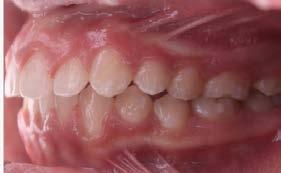

Objetivos: Conseguir clase I canina, controlar el crecimiento vertical, disminuir la convexidad esqueletal, reducir la sobremordida horizontal y mejorar el perfil facial. Caso clínico: Paciente femenina de 9 años, clase II esqueletal, biotipo dolicofacial, perfil convexo, clase II molar, clase II canina y proinclinación de incisivos superiores e inferiores. Resultados: Se logró clase I canina, se controló el crecimiento vertical, se redujo la convexidad esqueletal, se mejoró la sobremordida horizontal y el perfil facial. Conclusiones: El uso combinado de aparatos ortopédicos y aparatología fija en pacientes en crecimiento, junto con un diagnóstico y plan de tratamiento acertado, permite obtener resultados exitosos y estables en la corrección de estas maloclusiones.

Introducción: La maloclusión clase II provoca proporciones irregulares en el perfil facial. Puede deberse a un maxilar adelantado y a incisivos superiores proinclinados y protruidos. Esta condición puede corregirse mediante el uso de aparatos ortopédicos en pacientes en crecimiento.